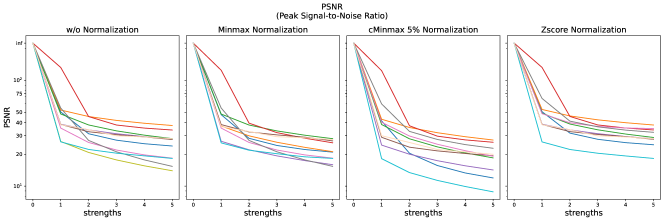

The results for all strengths are given in Figs. A.1-A.4. In Tab. 5 - 8, the results for distortions of maximal strength (s=5) are summarized.

For all applied distortions, all reference metric scores monotonously measure lower similarity for increasing distortion strengths.

PSNR scores generally display only very small changes for strengths larger than 2 (see Fig. A.1). PSNR values are higher for Zscore normalization.

Images distorted with Gaussian blurring and ghosting artifacts receive very high PSNR similarity scores, especially with small distortion strengths.

The experiments and adverse examples demonstrate specific strengths and weaknesses of the analyzed metrics. Although SSIM and PSNR are frequently used for the evaluation of synthetic MR images, they are strongly decreased by constant intensity shifts if no normalization is applied. PSNR is very dependent on the kind of normalization, which complicates its use as a comprehensive metric for comparing studies of different authors. SSIM underestimates blurring and thereby favors blurred or additionally blurred images over other distortions.